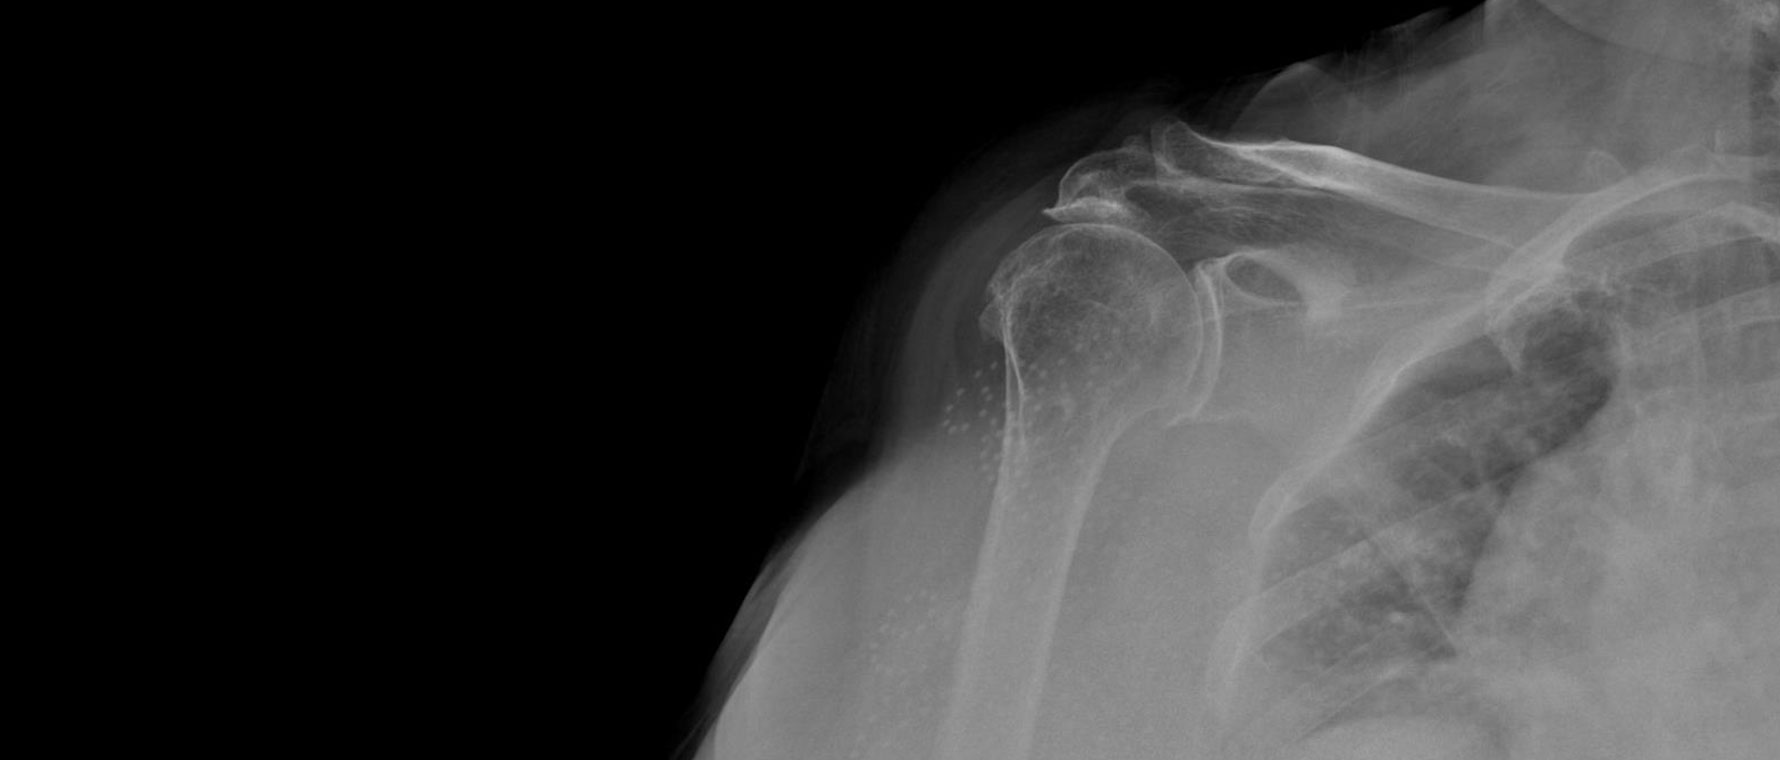

Omuz Kireçlenmesi

Omuz kireçlenmesi, omuz eklemindeki kıkırdağın zamanla aşınması sonucu gelişir. Hastalar omuzda derin ağrı, hareket kısıtlılığı ve gece ağrısından şikâyet eder. Saç tarama ve giyinme gibi hareketler zorlaşır. Tanı muayene ve röntgen ile konur. Tedavide ilaçlar, fizik tedavi ve enjeksiyonlar uygulanır. Şikâyetleri ileri düzeyde olan hastalarda cerrahi, özellikle omuz protezi seçenekleri gündeme gelir. Tedavinin amacı ağrıyı azaltmak, hareket açıklığını artırmak ve hastanın günlük yaşam kalitesini yükseltmektir.